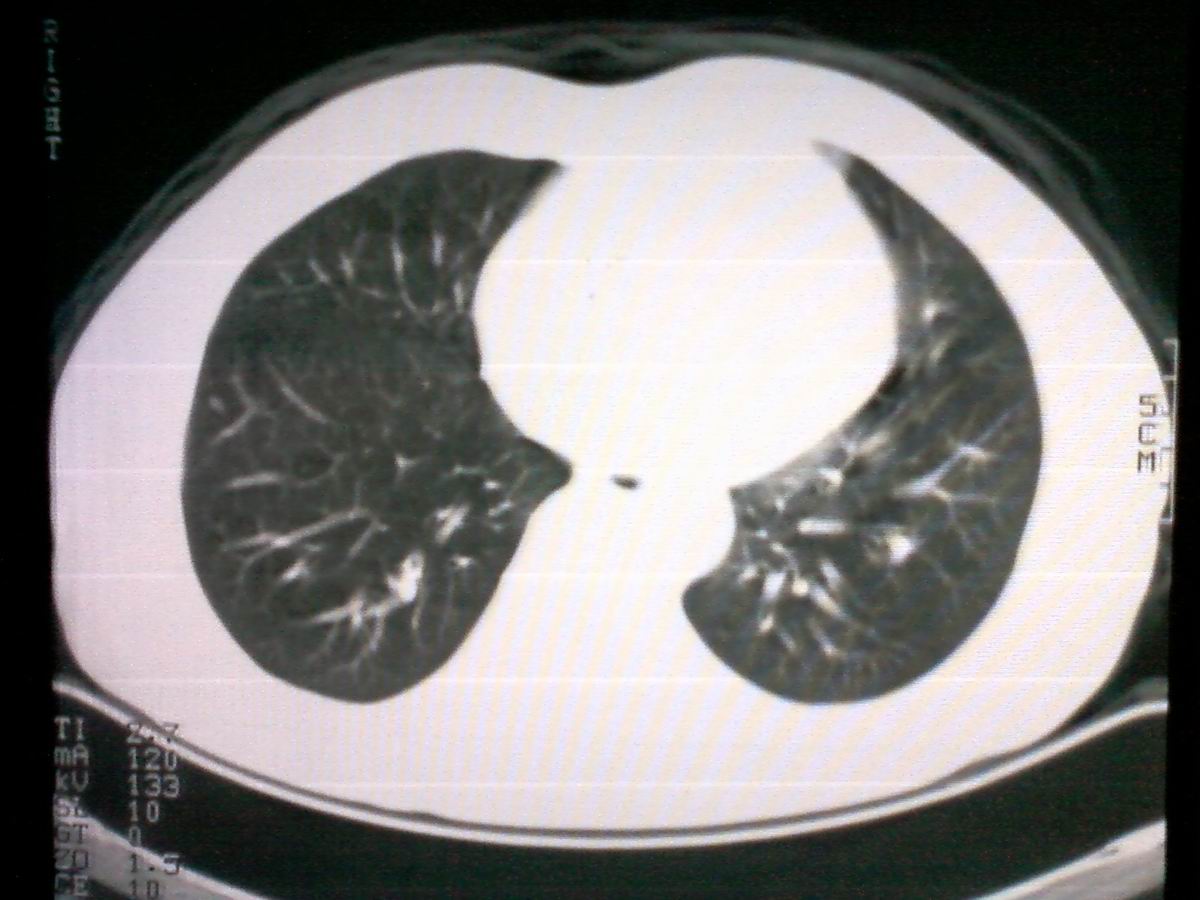

标题: CT25801:患者男性,65岁,临床提示双肺可闻及广泛罗音,看 [打印本页]

标题: CT25801:患者男性,65岁,临床提示双肺可闻及广泛罗音,看

仅见肺纹理影增重 纵膈淋巴结钙化